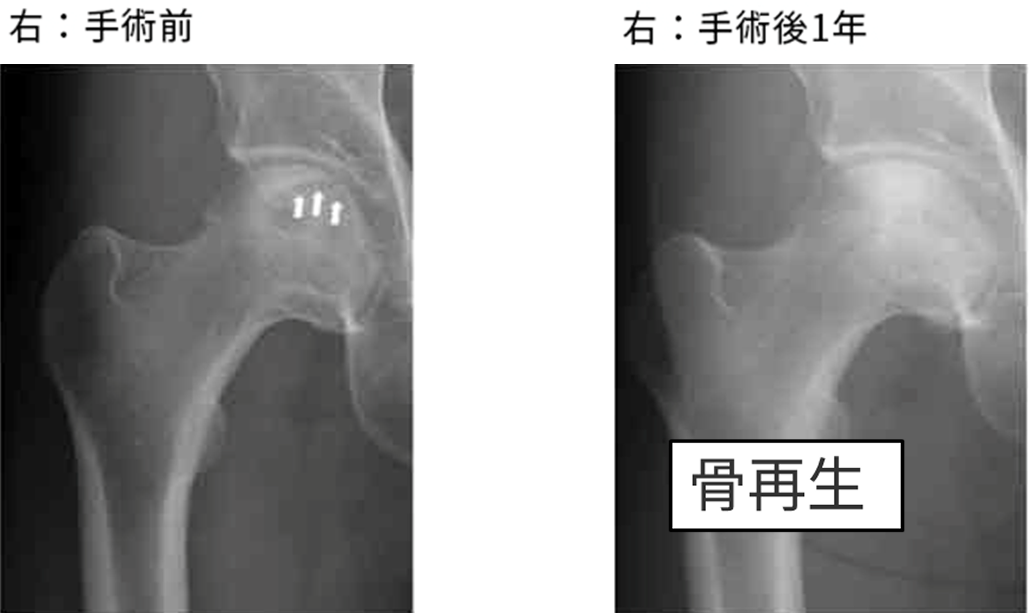

術前:骨頭内に左右とも骨折線のような黒い線(白矢印部分)が、骨頭の圧潰が進行中

術後1年:黒い線がなくなっており、骨頭内も白く、壊死部が再生